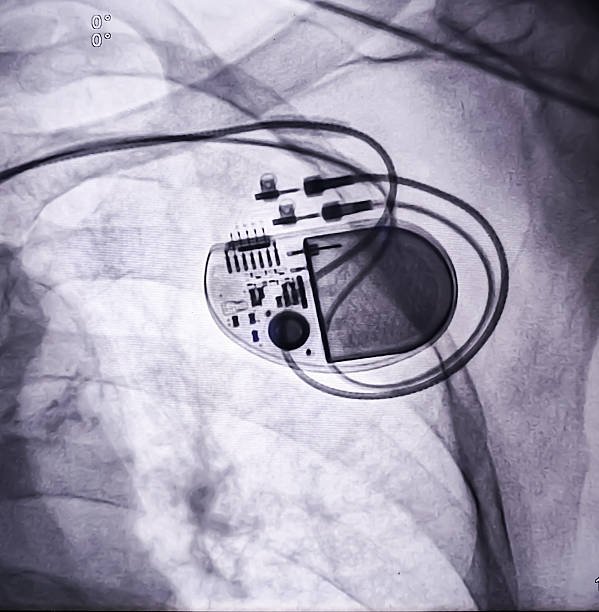

For example, cardiovascular implants like pacemakers and stents are widely used to manage heart-related conditions, while orthopedic implants help restore mobility in patients suffering from joint disorders.

Rapid innovations in medical technology are revolutionizing the implantable devices landscape. Developments such as miniaturization, smart implants, wireless connectivity, and advanced biomaterials are enhancing device performance, safety, and durability.

Modern implantable devices can now offer real-time monitoring and data transmission, enabling better patient management and personalized treatment. The integration of microelectronics and sensors is further expanding the capabilities of these devices.